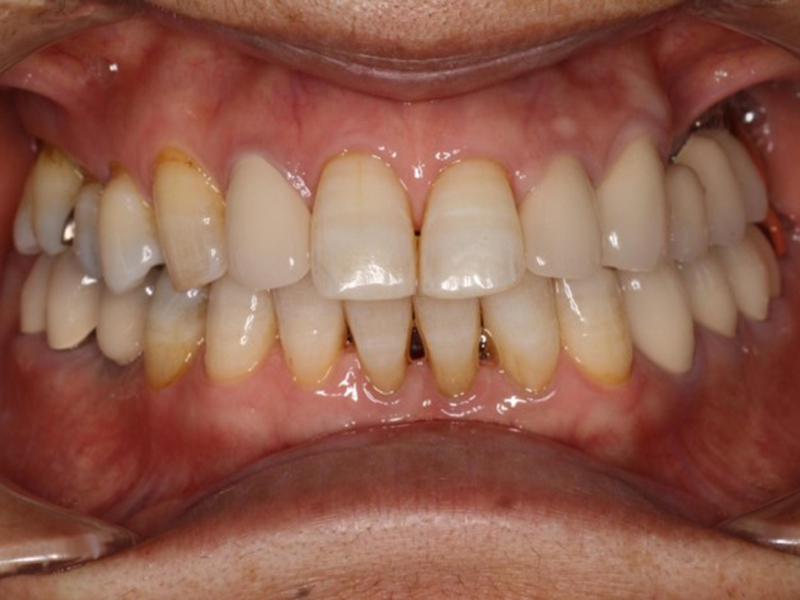

▼ ケース7 矯正終了→ホワイトニング→オールセラミックスによる修復

before

経過

after